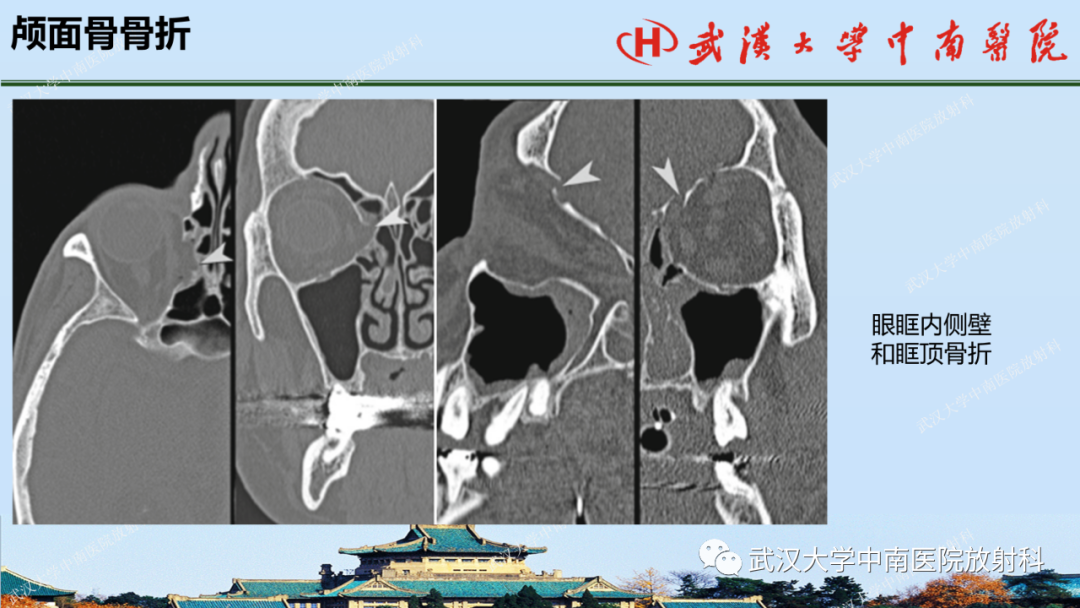

【PPT】脑外伤影像学诊断